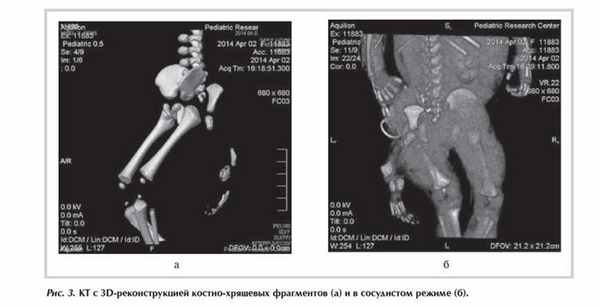

Данные КТ: к миелоцеле снизу и слева прилежит диспластичная дополнительная подвздошная кость, от которой отходят пучки мышечных волокон, идущие от ягодицы в дополнительную диспластичную нижнюю конечность, представленную аномально сформированными костно-хрящевыми структурами и пучками мышечных волокон. На расстоянии 19 мм от бифуркации аорты отходит подвздошная/бедренная артерия диаметром 1-1,5 мм, из которой дополнительная нижняя конечность получает кровоснабжение (рис. 3).